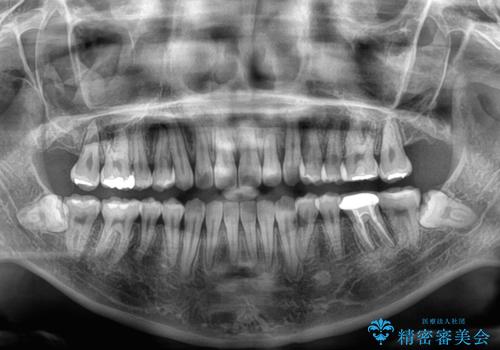

- 上顎の八重歯やデコボコを気にして来院された患者様です。

上顎歯列が狭窄していたため、急速拡大装置により上顎骨を側方に拡大しながら、ワイヤー装置にて矯正治療を行うこととしました。

上顎骨を拡大することで、八重歯やデコボコを歯列に収めることができ、下顎の歯が外に位置していた奥歯の咬み合わせも改善することができました。

スペースも短期間に獲得できるため、1年程度で治療を終えることができました。